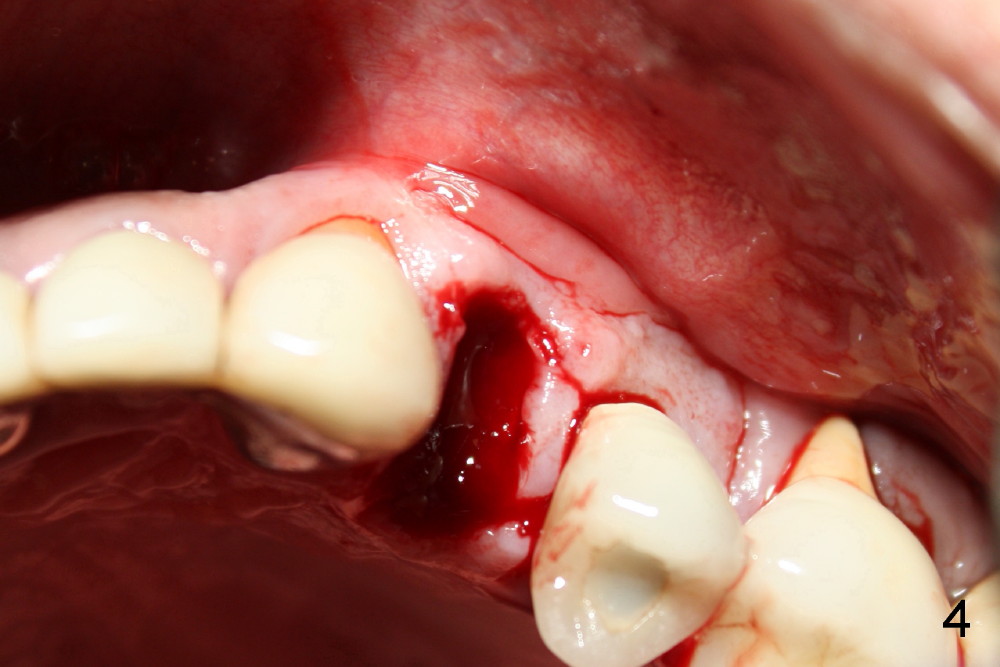

A 50-year-old man has mild pain in the upper left 1st bicuspid 3 years after root canal retreatment with placement of two posts (Fig.1). Findings of clinical exam are consistent with root fracture (Fig.2). Extraction reveals two fused roots (Fig.3,4). Probing indicates that the buccal plate is defective. Osteotomy is initiated in the palatal socket with a 2 mm pilot drill, followed by 2.5 and 3.0 mm reamers and 4.5x20 mm tap. The septum appears to have been pushed buccally (Fig.5 *) and form a new buccal wall (partially, strengthened by bone graft mentioned below) for the implant to be placed. The implant (4.5x20 mm) is placed in the palatal socket (Fig.6 *) with insertion of an abutment (A: 3.5x5 mm 0º), while a mixture of autogenous bone (harvested from reamers) and Synthograft (Bicon) is placed in the shrunken buccal socket (Fig.7; using allograft may decrease postop bony shrinkage). The bone graft is then contained by an immediate provisonal without collagen membrane or flaps. The patient is doing well postop. The gingiva is healthy (Fig.8*) when the provisional is removed 3 months postop with normal papillae (Fig.9 arrowheads). It remains the same 1 month post cementation (Fig.10,11). For further follow up, see immediate implant of the tooth #13.